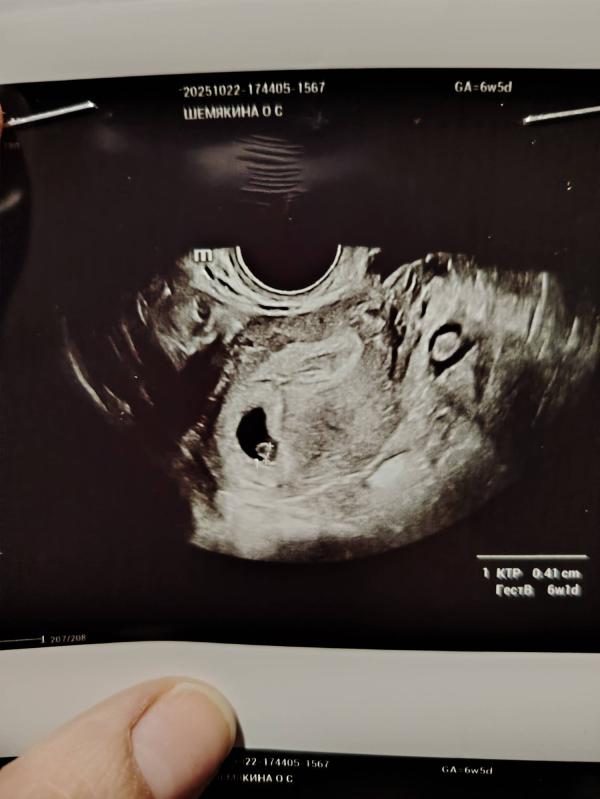

Сходили мы на узи. По узи срок на 4дня отстаёт от срока по месячным. Но думаю это норм. Дочка на 1,5 недели отставала... Человечк пульсирует, даже дали послушать чуток сердечко. Чсс пока не стали записывать. В пн узи в ЖК и плановый приём, наверно и на учёт поставят🙏❤️